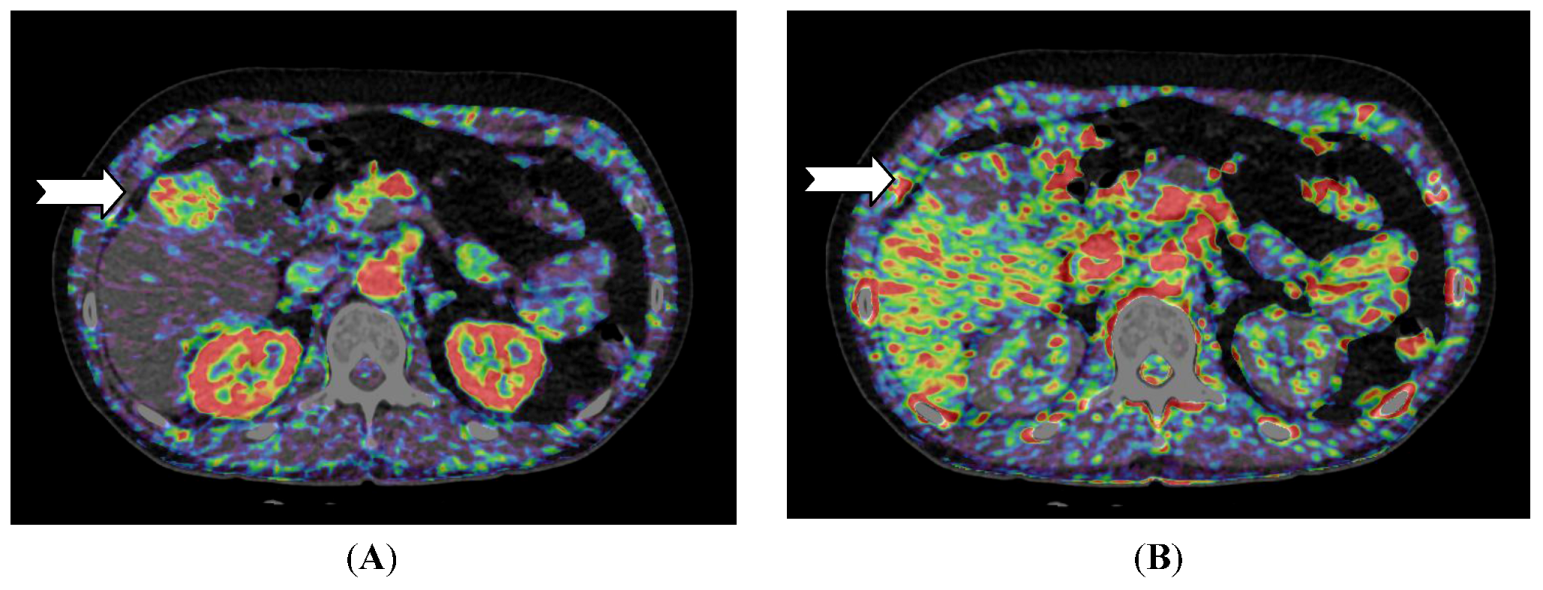

Figure 2.

CT perfusion examination of a 54-year-old male with a solitary hepatocellular carcinoma (HCC) in the right liver lobe (arrow). (A) Perfusion shows high arterial blood supply and (B) lower portal blood supply compared with surrounding normal liver tissue (Images reconstructed with Vitrea 6.2, Vital Images A Toshiba Medical Systems Group).